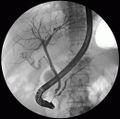

صورة للبنكرياس تظهر قناة المعثكلة و الشجرة الصفراوية.

2-قناة صفراء داخل الكبد

3-قنوات كبدية يمنى ويسرى

4-قناة كبدية مشتركة

5-قناة المرارة

6-القناة الصفراوية المشتركة

7-أمپولة ڤاتر

8-الحليمة الإثناعشرية الرئيسية

9-المرارة

10،11-الفصين الأيمن والأيسر للكبد

12-الطحال

13-المريء

14-المعدة والأمعاء الدقيقة

15-الپنكرياس

16-ملحق قناة الپنكرياس

17-قناة الپنكرياس

18-أمعاء دقيقة

19-العفج

20-الصائم

21،22-خيال الكليتان اليمنى واليسرى.